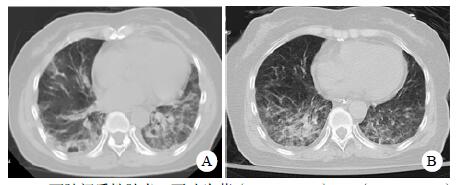

患者,女,54岁,工人,因“头晕5 d”于2019年9月29日至浙江大学附属第二医院急诊就诊。5 d前患者无明显诱因出现头晕,伴行走不稳、四肢乏力,无发热、咳嗽咳痰、胸闷气促、恶心呕吐、四肢抽搐等,未就诊。我院急诊头颅磁共振(MRI)示:右侧丘脑及左侧岛叶异常信号,局部累及右侧中脑(图 1),考虑脑多发占位性疾病。在急诊抢救室予甘露醇100 mL静滴脱水降颅压等对症治疗,5 h后患者逐渐意识模糊。急查血常规:白细胞16.1×109/L,中性粒细胞百分比73.4%;头颅CT示右侧丘脑、左侧岛叶病变,伴脑室扩张(图 2);急诊行“双侧脑室外引流术”,术中引流液呈淡血性。术后诊断:⑴(右侧丘脑)颅内占位性病变,脓肿首先考虑,肿瘤需排除;⑵脑积水;⑶脑疝。患者带气管插管转入ICU进一步治疗。当时体温38.3℃,脉搏99次/min,呼吸频率24次/min,血压169/87 mmHg(1 mmHg= 0.133 kPa),颈软,神志昏迷,右侧瞳孔3 mm,左侧瞳孔2.5 mm,对光反射迟钝。双肺呼吸音粗,可闻及少量啰音。左侧病理征阳性。患者3个月前曾因“反复胸闷气促伴发热1个月余”在本院风湿科住院,当时胸部高分辨CT示两肺间质性肺炎、下叶为著(图 3);血化验示血沉偏高,抗心磷脂抗体阳性;诊断为“间质性肺炎”,住院期间予甲泼尼龙40 mg/d静滴×8 d,60 mg/d静滴×6 d,共住院14 d;出院后予口服甲泼尼龙40 mg/d联合雷公藤多苷片每次20 mg,一日2次治疗;此后规范于本院门诊复诊。本次起病前2个月甲泼尼龙已减量至36 mg/d口服治疗。

| 右侧丘脑及左侧岛叶异常信号,局部累及右侧中脑 图 1 患者2019-09-29头颅MRI平扫+黑水成像 |